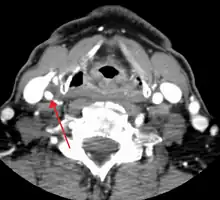

One of several different imaging modalities, such as a computed tomography angiogram (CTA)[18][19][20] or magnetic resonance angiogram (MRA) may be useful. Each imaging modality has its advantages and disadvantages - Magnetic resonance angiography and CT angiography with contrast is contraindicated in patients with chronic kidney disease, catheter angiography has a 0.5% to 1.0% risk of stroke, MI, arterial injury or retroperitoneal bleeding. The investigation chosen will depend on the clinical question and the imaging expertise, experience and equipment available.[21]

Based on the NASCET (The North American Symptomatic Carotid Endarterectomy Trial) criteria, the degree of carotid stenosis is defined as:[22]

- percent stenosis = ( 1 − ( minimum diameter within stenosis) / ( poststenotic diameter ) ) × 100%.